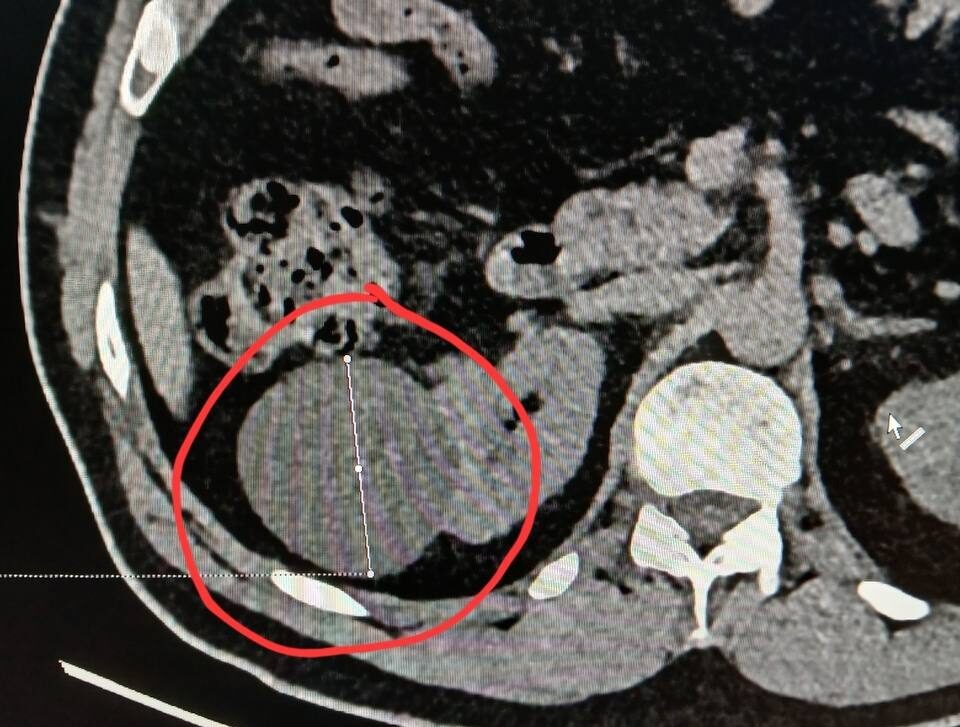

По словам главы Минздрава Карелии, частая находка на мужском чекапе — киста почки. Оь этом он сообщил в своем телеграм-канале.

«Киста почки при компьютерной томографии визуализируется как объёмное жидкостное образование округлой формы с чёткими ровными контурами. Ключевым диагностическим критерием является характеристика её содержимого и поведение при контрастном усилении», — рассказал Михаил Охлопков.

Сложные кисты требуют, по его словам, особого внимания. Наличие перегородок, утолщение стенок, кальцинаты могут привести к онкологии. Поэтому такие кисты могут потребовать хирургического вмешательства.